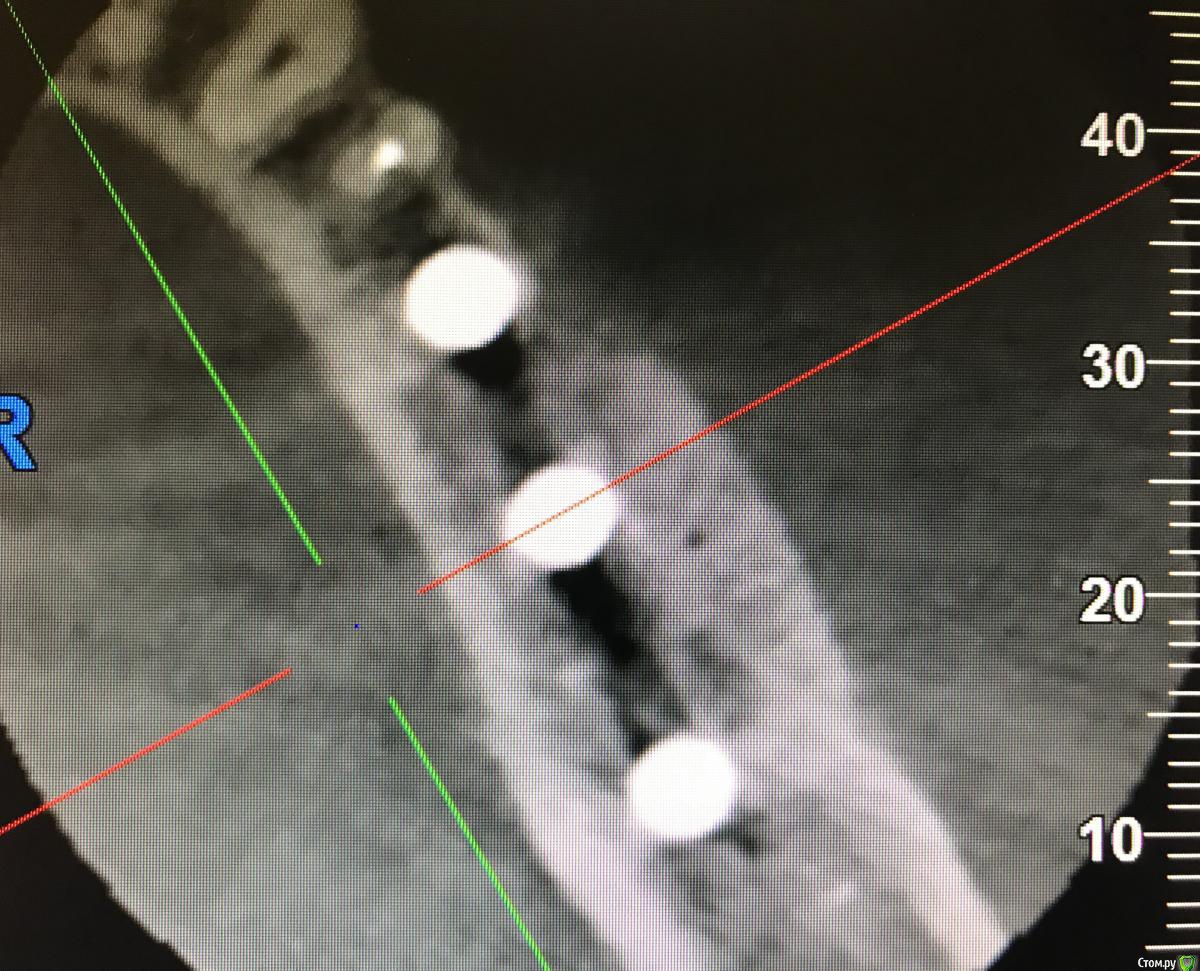

колесников Опубликовано 15 марта, 2019 Автор Поделиться Опубликовано 15 марта, 2019 Вот так выглядит интегрированый графт и соответственно не созревший. Время ожидания примерно равнозначное Ссылка на комментарий

Bier Опубликовано 15 марта, 2019 Поделиться Опубликовано 15 марта, 2019 а на каком уровне срез? Ссылка на комментарий

колесников Опубликовано 15 марта, 2019 Автор Поделиться Опубликовано 15 марта, 2019 По середине Ссылка на комментарий